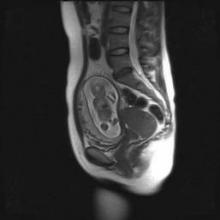

Courtesy Dr. Frédéric Amant

This woman's pregnancy was complicated by spinocellular cervical cancer stage 1b. After chemotherapy, she underwent cesarean section at 33 weeks.